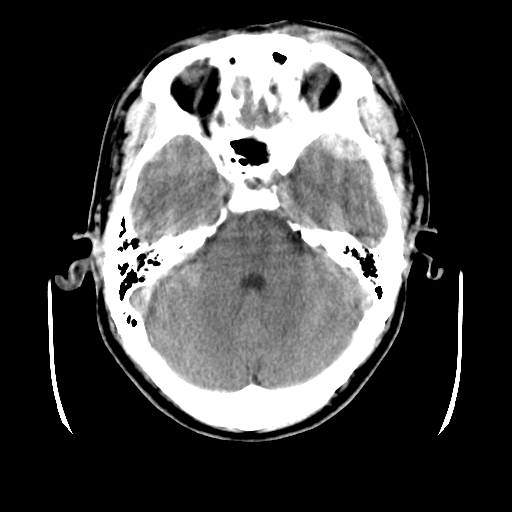

男,51岁,头外伤一小时,呕吐两次。

蛛网膜下腔出血 脑肿胀

左侧颞部硬膜外;蛛网膜下腔出血 ;脑肿胀

1)左侧中颅窝蝶骨翼后方硬膜外血肿。2)左侧颞顶部硬膜下血肿。3)蛛网膜下腔出血。4)左侧筛窦及双侧蝶窦炎症(或积血)。5)左侧额部头皮软组织肿胀。

蛛网膜下腔出血

左侧硬膜外 下血肿  硬膜下血肿影不出外是蛛网膜下腔出血

左颞顶不头皮血肿,左侧颞不硬膜(下)血肿,蛛网膜下腔出血

1:左侧硬膜外及硬膜下混合血肿。2:蛛网膜下腔出血。3:左额部少量颅内积气?

左颞部硬膜外血肿,蛛网膜下腔出血,副鼻窦积液.头皮损伤.